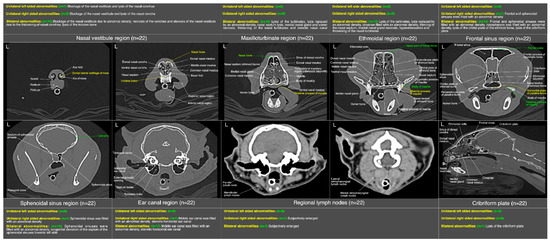

The most prominent abnormality observed in nasal vestibule region was unilateral/bilateral mild to moderate pathological necrosis of the nasal conchae, noticed in 23% (n = 5) of cases, as shown in Figure 8d–f. Unilateral severe blockage of the nasal vestibule by an iso-attenuating density and bilateral severe blockage by an iso-/mixed-attenuating density [Figure 8g–i] was noticed in 18% (n = 4) cases for each category. Other most common abnormalities were bilateral moderate to severe thickening of the nasal conchae [Figure 8b], unilateral/bilateral stenotic nares [Figure 8a] and bilateral mild to moderate increase in the width of palatine fissure [Figure 8h] seen in 9% (n = 2), 14% (n = 3) and 9% (n = 2) cases, respectively. In terms of laterality and any affected structure(s), bilateral nasal vestibule abnormalities (Figure 14) were cumulatively recorded in 64% (n = 14) cases in localized CT scan abnormalities of this region.

In maxilloturbinate region, bilateral severely occupied nasal passage with an abnormal density excluding maxillary sinuses [Figure 9e,f] in 41% (n = 9) cases and distortion of the medial nasal gland [Figure 9c] in 36% (n = 8) cases followed by severe bilateral lysis of the maxillary turbinates [Figure 9c–f] in 32% (n = 7) cases and bilateral severely filled maxillary sinuses with an abnormal density [Figure 9c] in 27% (n = 6) cases were predominant findings. Mild lysis of the nasal septum was noticed in 27% (n = 6) cases. Distortion of the vomer bone [Figure 9d] of this region and unilateral/bilateral moderate lysis of the turbinates were noticed in 23% (n = 5) cases for each category. Moderate to severe thickening of the maxillary turbinates with/without hyper-attenuation and unilateral/bilateral severely stenotic nasal passage(s) [Figure 9a] due to severe thickening of the maxillary turbinates were noticed in 9% (n = 2) and 14% (n = 3) cases, respectively. In terms of localized findings of this region, again, bilateral abnormalities (Figure 14) were recorded in 68% (n = 15) cases, and unilateral left or right sides were not affected in any case.

In ethmoidal region, a bilateral moderate to severe lysis of the turbinates including basal laminae of the ethmoid bone [Figure 10a–c] in 55% (n = 12) cases was a predominant finding. Severe infiltration of the bilateral nasal passages and choanae of this region with an abnormal space occupying soft tissue/fluid density [Figure 10g–i] were seen in 32% (n = 7) of the cases. Distorted medial nasal gland [Figure 10a], bilateral moderate thickening of the ethmoidal turbinates with/without hyper-attenuation and partial lysis of the nasal septum [Figure 10c] were recorded in 27% (n = 6), 18% (n = 4) and 9% (n = 2) cases, respectively. As concerned with the localized findings of this region, here also bilateral abnormalities (Figure 14) were predominant findings and recorded in 64% (n = 14) cases and unilateral left or right side was not affected in any case.

In frontal sinus region, unilateral/mild to moderate bilateral infiltration of the frontal and sphenoidal sinuses with an abnormal soft tissue/fluid density was noticed in 45% (n = 10) and 32% (n = 7) cases, respectively. While severe infiltration of these sinuses with an abnormal soft tissue/fluid density [Figure 11a–d] was recorded in 9% (n = 2) for frontal sinuses and 23% (n = 5) cases for sphenoidal sinuses. Lysis of the cribriform plate [Figure 11a,b] and surrounding bony structures was noticed in 5% (n = 1) cases from each category. A mild to moderate infiltration of the nasopharynx [Figure 11a,d] with an abnormal soft tissue/fluid attenuating density was noted in 9% (n = 2) cases. Emphysematous fascial planes of the neck region were also recorded in 9% (n = 2) cases. In the summary of localized CT scan abnormalities (Figure 14) of this region, bilateral frontal and sphenoidal sinuses were affected in 64% (n = 14) and 45% (n = 10) cases, respectively. Unilateral right side was affected in one case only for both sinuses of this region. On the other hand, left side was not affected in any case for both frontal and sphenoidal sinuses. A single case of bilateral cribriform lysis was also recorded for this region (Figure 14).

Thickening of the first/second/third generation bronchial wall(s) [Figure 12a] was the predominant finding in thoracic region and observed in 36% (n = 08) cases. Calcification of the bronchial walls [Figure 12e] was present in one case only. Mild mosaic pattern [Figure 12f] of any lung lobe(s) and mild to moderate peribronchovascular interstitium thickening [Figure 12f] was noticed in 18% (n = 4) cases for each category. A ground-glass opacification (GGO) pattern [Figure 12d] of any lung lobe was recorded in 23% (n = 5) cases. Mild crazy-paving pattern [Figure 12b], mild traction bronchiolectasis in any lung lobe, and consolidation of any lung lobe was noticed in 9% (n = 2) cases for each category. Other uncommon findings were collapsed lung lobe(s) and pneumomediastinum, recorded in a single case for each category. In the summary of localized CT scan findings of pulmonary parenchyma (Figure 15), subjectively thickened bronchial walls of all lung lobes 36% (n = 8) followed by GGO 14% (n = 3) and mosaic patterns of left caudal lung lobe 14% (n = 3) and mosaic pattern of right caudal lung lobe 14% (n = 3) were predominant findings.

In additional CT scan findings, severe infiltration of the bilateral middle ear canal with an abnormal density was noticed in 36% (n = 08) cases, while moderate bilateral infiltration was recorded in 14% (n = 3) cases. A subjective mandibular lymphadenomegaly was noticed in 9% (n = 2) of the cases. In the summary of localized CT scan abnormalities (Figure 14) of ear canal and regional lymph nodes, bilateral middle ear canal was affected in 50% (n = 11) cases, while bilateral mandibular lymphadenomegaly was recorded in one case only. On the other hand, Unilateral right-sided abnormality of the middle ear canal and mandibular lymph node was recorded in one case only. Abnormality of unilateral left-sided ear canal and regional lymph node was not recorded in any case.

Figure 14. An illustrative summary of the localized computed tomographic abnormalities at focused regions of the skull in terms of their laterality in a total of 22 cats presented with acute/chronic infectious respiratory disease signs.

Figure 15. An illustrative summary of the localized computed tomographic abnormalities of the pulmonary parenchyma (individual lung lobes and lobules) and their relevant blood vessels in terms of their laterality in a total of 22 cats presented with acute/chronic infectious respiratory disease signs.

Figure 16. An illustrative summary of the localized radiographic abnormalities (patterns) of the pulmonary parenchyma (individual lung lobes and lobules) and their relevant blood vessels in terms of their laterality in a total of 27 cats presented with acute/chronic infectious respiratory disease signs.